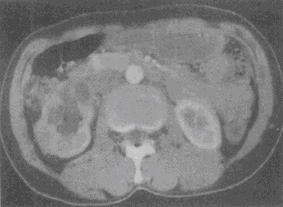

患者,男,33岁,尿频,尿急伴发热月余。尿常规检查:镜下血尿,脓尿。CT检查见图。该患者最有可能患何种疾病

患者,男,33岁,尿频,尿急伴发热月余。尿常规检查:镜下血尿,脓尿。CT检查见图。该患者最有可能患何种疾病<img border="0" style="width:

[单选题]患者,男,33岁,尿频,尿急伴发热月余。尿常规检查:镜下血尿,脓尿。CT检查见图。该患者最有可能患何种疾病A.肾癌B.肾盂癌C.肾结核D.肾囊肿E.错

患者,男,33岁,尿频,尿急伴发热月余。尿常规检查:镜下血尿,脓尿。CT检查见图。该患者最有可能患何种疾病<img border="0" style="width:

[单选题]患者,男,33岁,尿频,尿急伴发热月余。尿常规检查:镜下血尿,脓尿。CT检查见图。该患者最有可能患何种疾病A.肾癌B.肾盂癌C.肾结核D.肾囊肿E.错

患者,男,33岁,尿频,尿急伴发热月余。尿常规检查:镜下血尿,脓尿。CT检查见图。该患者最有可能患何种疾病( )。<br /><img border="0" s

[单选题]患者,男,33岁,尿频,尿急伴发热月余。尿常规检查:镜下血尿,脓尿。CT检查见图。该患者最有可能患何种疾病( )。图1图2图3A.肾癌B.肾盂癌C.

患者,男,33岁,尿频,尿急伴发热月余。尿常规检查:镜下血尿,脓尿。CT检查见图

[单选题]患者,男,33岁,尿频,尿急伴发热月余。尿常规检查:镜下血尿,脓尿。CT检查见图。该患者最有可能患何种疾病()A . 肾癌B . 肾盂癌C . 肾结核D . 肾囊肿E . 错构瘤